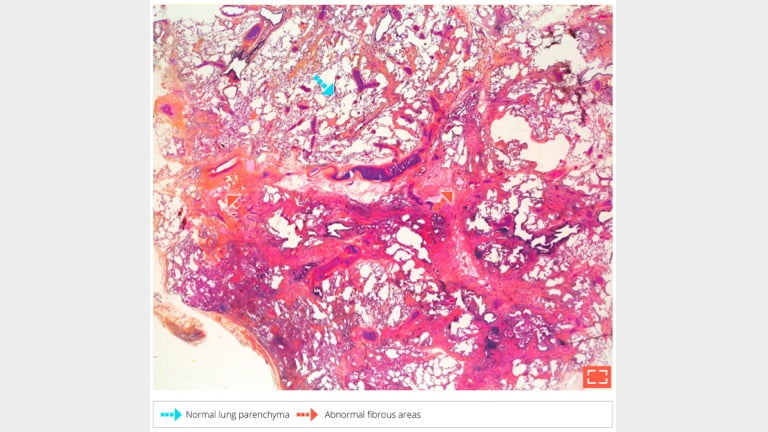

• Disseminated, non uniform patchwork pattern of interstitial fibrosis

• Non-uniform, heterogeneous appearance with alternation between abnormal fibrotic areas and apparently normal lung parenchyma at low-magnification.

• The juxtaposition of abnormal areas and normal areas resembles a patchwork, hence the term “patchy”.

• Topographic diagnosis at low-magnification